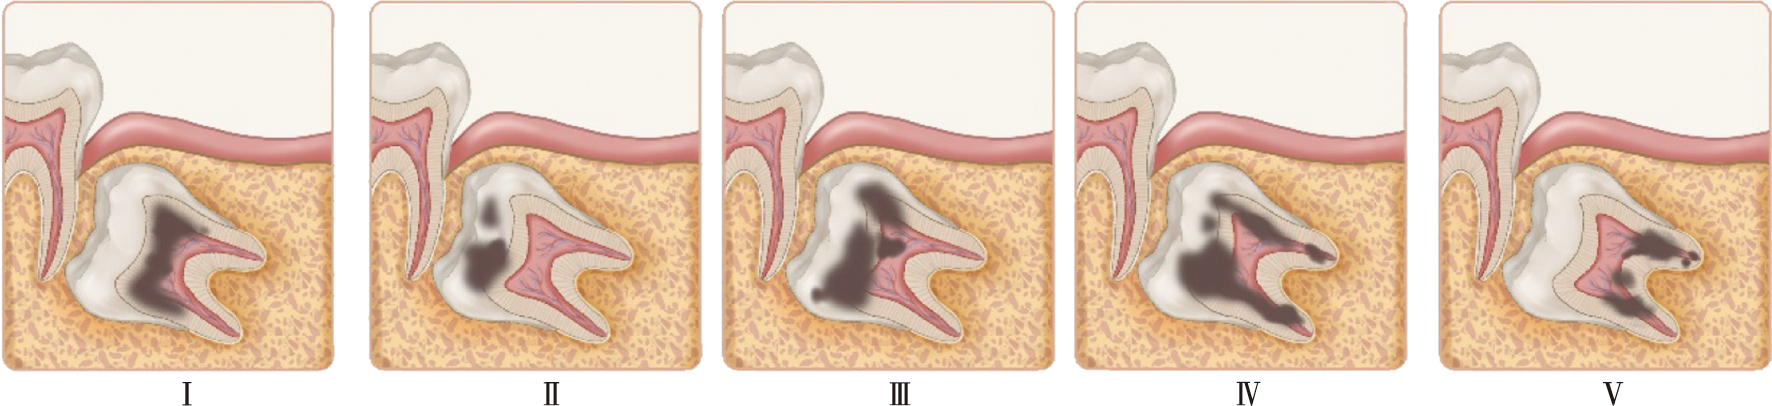

Abbott PV, Lin S. Tooth resorption-part 2: A clinical classification[J]. Dent Traumatol, 2022, 38(4): 267-285.

李雪滢, 邹晓英, 岳林. 牙吸收诱发因素与临床诊治策略[J]. 口腔医学, 2023, 43(4): 289-293, 321.